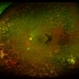

- 56-year-old man, BCVA 20/25. Incidental finding. Laser was given.